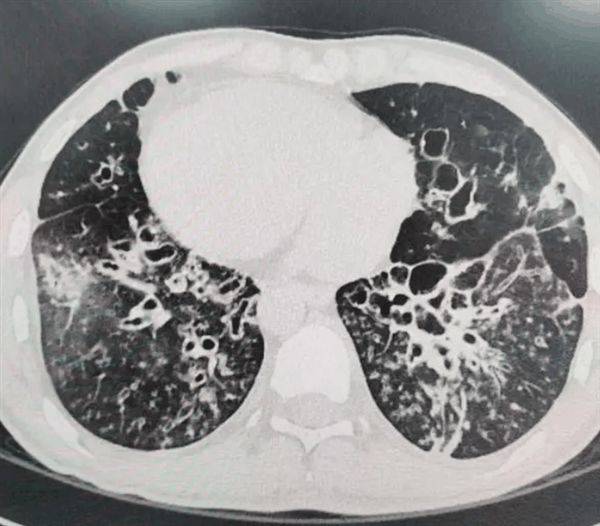

• 发现率百万分之一!小伙肺上感染久治不愈 检查竟是镜面人

叮当号9月24日消息,据媒体报道,湖北的肖先生(化名)因反复咳嗽多年,始终不能治愈,上周因病情加重来到武汉市肺科医院治疗。 医生经过检查发现,肖先生竟是罕见的“镜面人”,即其体内所有内脏器官的排列顺序与正常人完全相反,这种特殊体质在医学界被称为“全内脏反位”,其发病率极低,仅为百万分之一。 “镜面人…